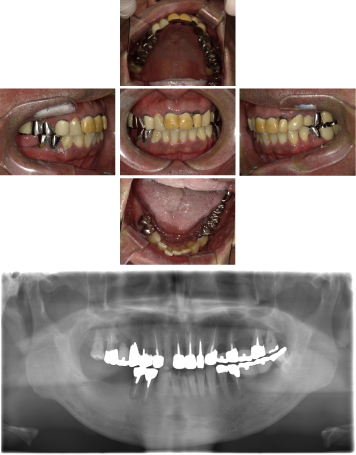

50代 インプラント治療(右上3左上3のみGBR)

| 主訴 | 入れ歯が合わず毎日ヨーグルトしか食べることができないので、しっかり咬めるインプラントにしたい。 |

| 部位 | 右下⑦⑥5④ 上顎③2①①2③ 左下67 |

| 治療期間 | 約9ヶ月 |

| 費用 | ¥4,273,500(税込) |